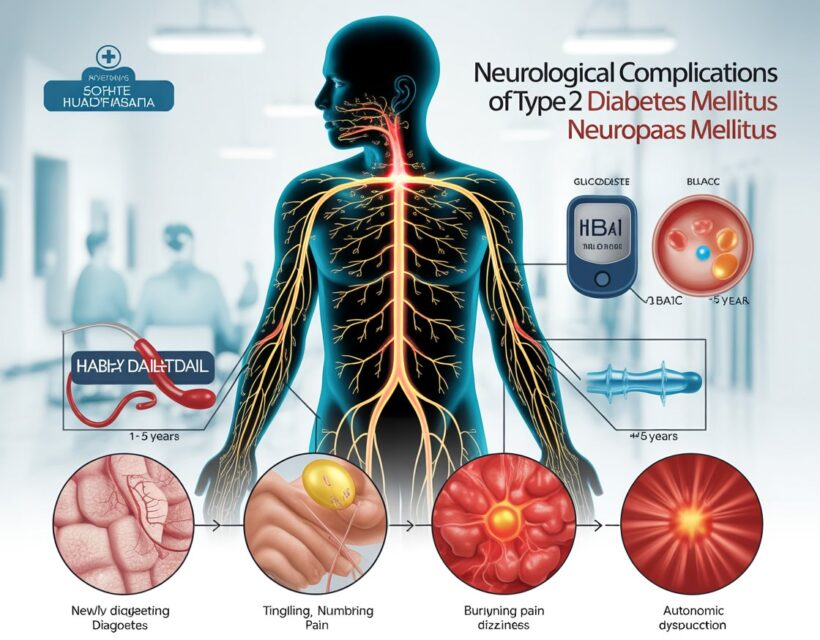

Neurological Complications of Type 2 Diabetes Mellitus: A Duration-Based Comparative Study at a Secondary Care Hospital in Karachi, Pakistan

Authors: Muhammad Adil Ramzan • Hamda Rehman • Bhavesh Kumar •…